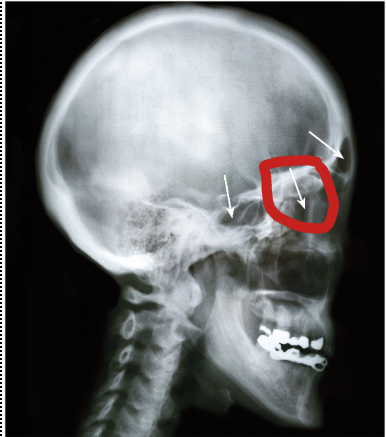

frontal sinus

sphenoidal sinus

ethmoid sinus

maxillary sinus

how does a sinus headache occur?

inflamed and swollen mucous membrane blocking mucus secretions from draining

sinus function

reduces weight of skull